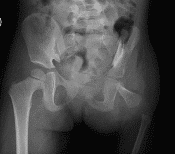

Proximal femoral focal deficiency and congenital short femur are thought to be versions of the same problem, also known as congenital femoral deficiency. These conditions both affect the femur (the thigh bone). With congenital short femur, the bone can appear almost normal on an x-ray. However, it is shorter than the other side. In some children, the difference in length is not noticed until they are a few years old or even until adolescence. However, in other children, the leg length difference can be noticed shortly after birth (Figure 1).

Figure 1: (A) This is an x-ray of the both legs of a 4 year old female with proximal femoral focal deficiency. Notice that the left leg is much shorter than the right and that the shape of the left femur (noted by *) is very different than the right. (B) 11 year old male with right congenital short femur. Unlike 1A, the right femur in this child (*) looks very similar to the left side and he has only a 4.5cm difference in the length of his right leg compared to the left.

With proximal femoral focal deficiency, the femur shape is also affected and can be significantly shorter than the other side. On x-ray, the portion of the femur that is closer to the hip joint can appear severely angled, it may be mostly made of cartilage and therefore difficult to see on an x-ray when a child is very young, or the proximal femur may be absent (Figure 2). Congenital short femur and proximal femoral focal deficiency are thought to be part of the same spectrum of pathology, with congenital short femur often being less severe than proximal femoral focal deficiency. The following article is meant to be a brief overview of these diagnoses and potential treatment options and is not meant to be a comprehensive review of all possible surgical and nonsurgical treatments.

Figure 2: Pelvis x-ray of a 2 year old female with severe left proximal femoral focal deficiency, where the proximal portion of the left femur did not develop.